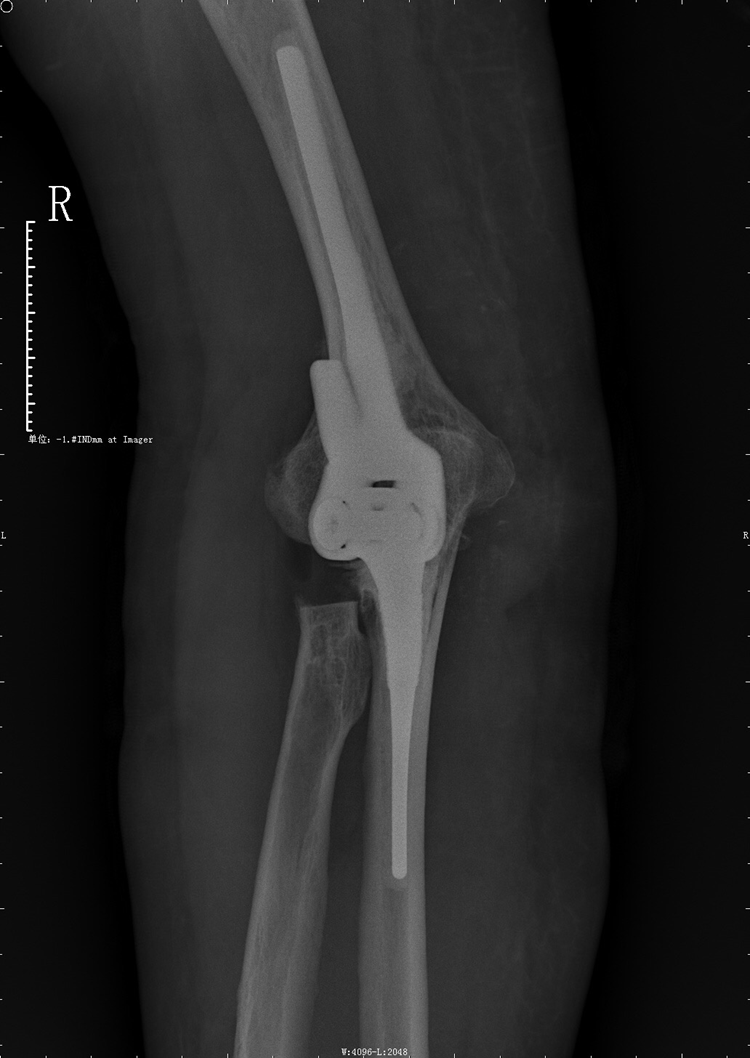

近日,我院骨伤科采用人工全肘关节置换术,成功为一名重度骨关节炎患者实施了手术,术后患者恢复良好。该技术为我院首例,它标志着我院骨伤科在骨科疼痛治疗领域又一次突破。

据了解,该患者15年来一直饱受右侧肘关节疼痛、活动障碍的困扰,近一个月来疼痛加重,生活起居严重受限。入院行相关检查后诊断为重度骨关节炎伴屈曲畸形,我院骨伤科手术团队经过反复分析与研究,决定为该患者施行右侧人工全肘关节置换术,仅用两小时成功完成手术。

与其它人工关节相比,全肘关节置换术是目前世界上开展相对较少的手术,对手术医师的操作准确性要求非常高,并且对软组织平衡及假体的匹配要求非常精准,但施行人工全肘关节置换术能极大地减少患者痛苦,降低经济负担,并缩短病程时间,同时这也是我院骨伤科手术团队在累计完成数百例髋、膝关节置换及肩关节置换手术的基础上开展的新手术方法,标志着我院院骨伤科在肘关节疾病手术治疗技术方面达到国内先进水平,为我市肘关节病人提供新的治疗方案,填补了我院肘关节置换方面的空白。(投稿/骨伤科 杨经慧)